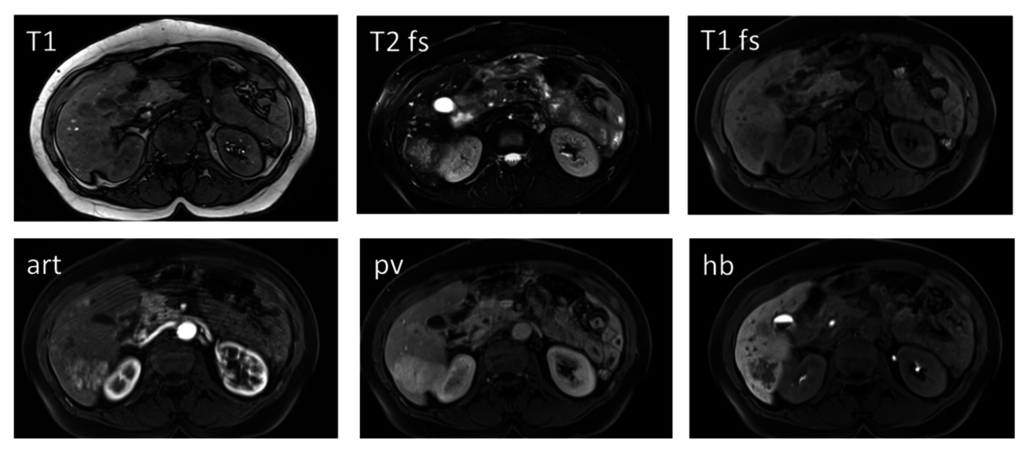

3. Magnetic Resonance Imaging (MRI)

3.1. Hepatocyte Specific MRI Contrast Agents

3.2. Diffusion-Weighted MR Imaging

3.3. Dynamic Contrast Enhanced MRI